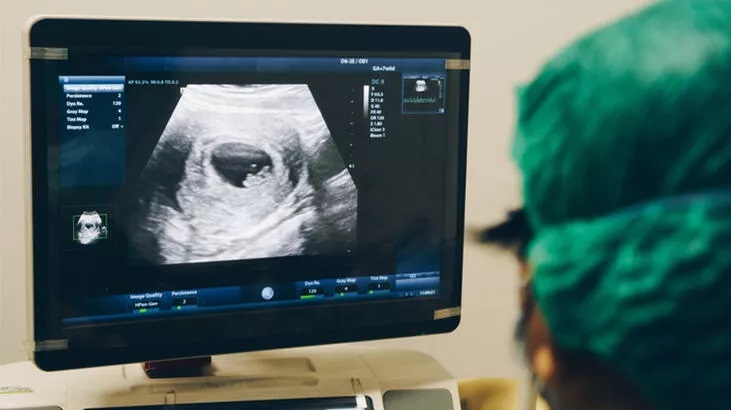

Doktorlar, Pompe hastalarında eksik olan bir enzimi vermek için Ayla’nın annesine hamileliğinin 24. ve 37. haftaları arasında altı infüzyon verdi. Bebekte eksik olan enzim, ultrason tarafından yönlendirilen iğneler kullanılarak fetal göbek kordonu damarına enjekte edildi.

Ottawa Hastanesindeki doğum öncesi enzim replasman tedavisinden sonra Ayla, 22 Haziran 2021’de dünyaya geldi. Ayla’da yapılan testler, kalp ve kas gelişiminin normal olduğunu gösterdi.